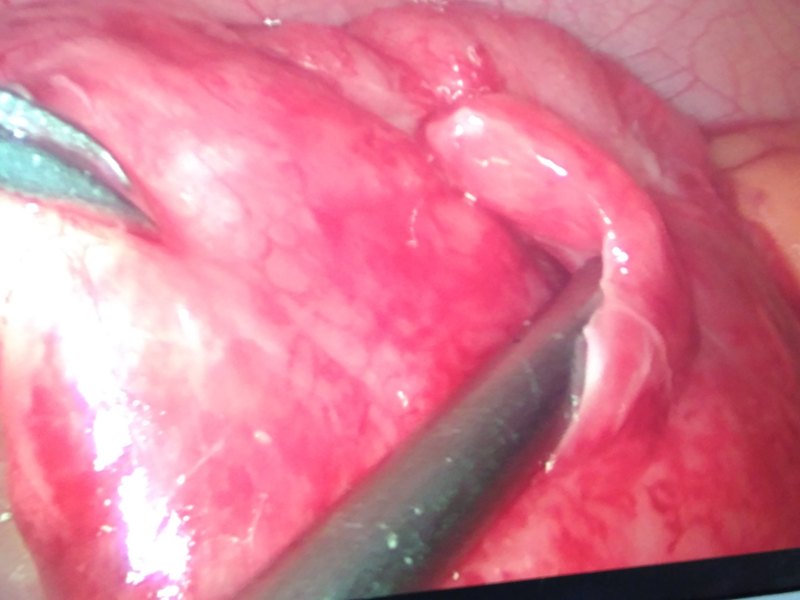

异位阑尾炎的微创治疗避免了拉链式的延长切口异位阑尾的患者,腹腔镜手术是您的福音曾经许多主任觉得阑尾炎腹腔镜手术完全没有必要,开腹手术切口也不大,并发症也不多。到遇到异位阑尾,肥胖患者,弥漫性腹膜炎等特殊情况时,往往需要大的延长切口,创伤极大术后感染肠梗阻等并发症明显增多!随着微创理念深入人心,医师在操作水平提高,患者的观念认知改变,微创手术给患者带来非常大的好处,异位阑尾在术前较难发现其位置,因此阑尾位于肝下,后腹膜,左下腹和盆底时,腹腔镜能快速找到阑尾并于切除,术后恢复快并发症少!是这类特殊患者的首选手术方式!